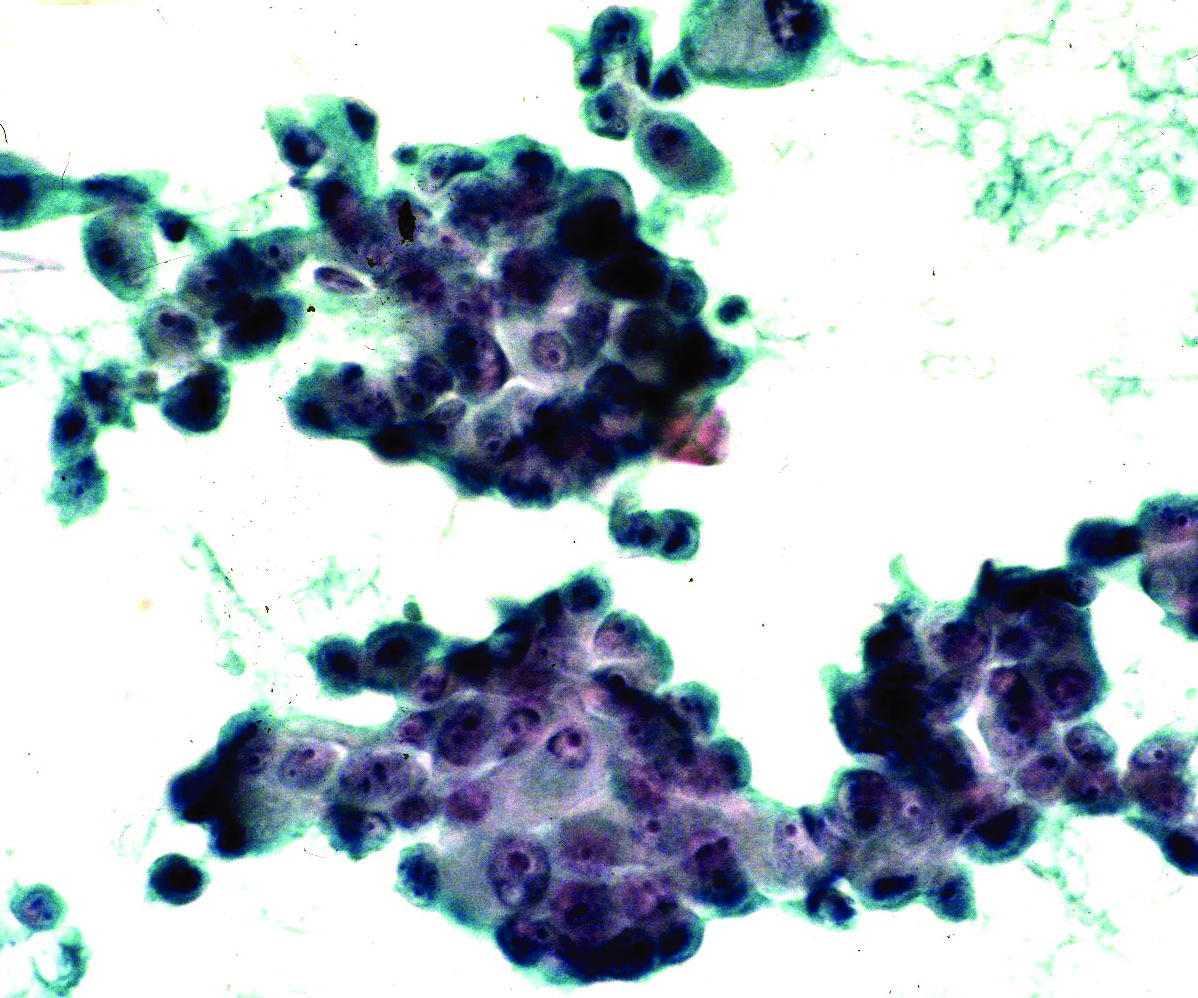

Cytology description

- Can use cellular pleomorphism, nuclear size, nuclear margin, nucleoli, lack of naked nuclei, cellular dyscohesion and mitoses in addition to necrosis to assess cytologic tumor grade, which correlates with histologic grade (Diagn Cytopathol 2003;29:185)

Cytology images